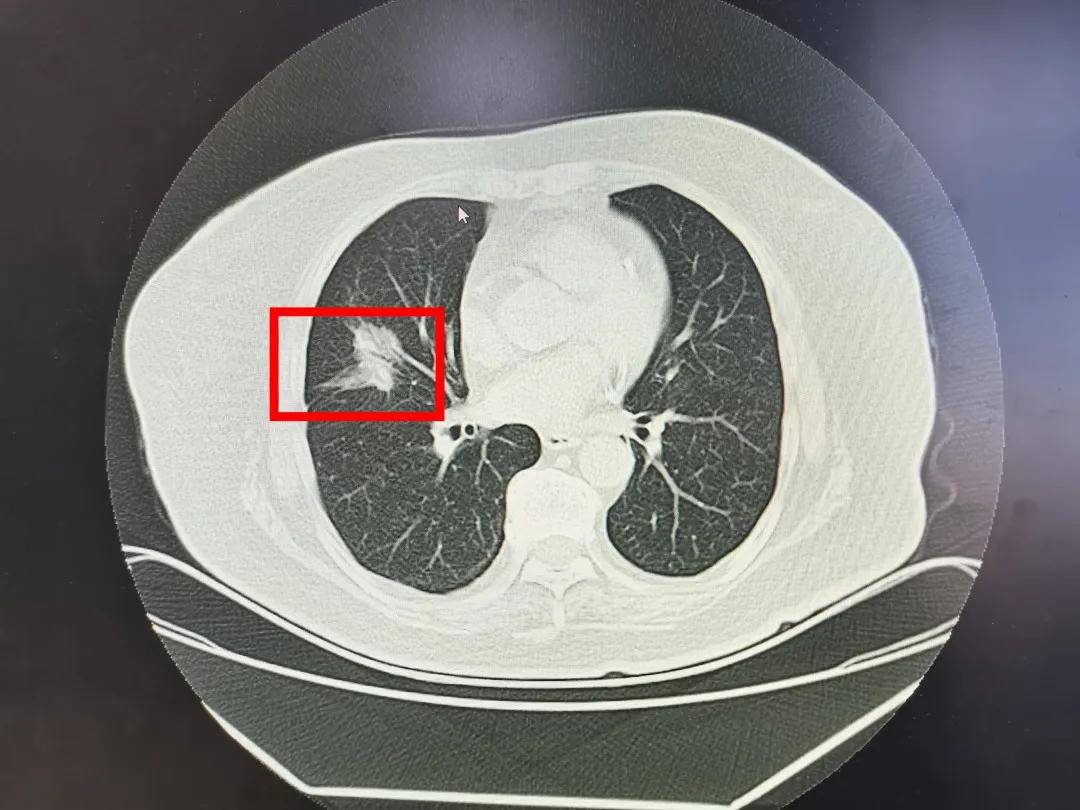

这是今天微创手术病人,男,55岁,咳嗽一个月一照片就发现肺癌,已不是

图片尺寸2373x1530